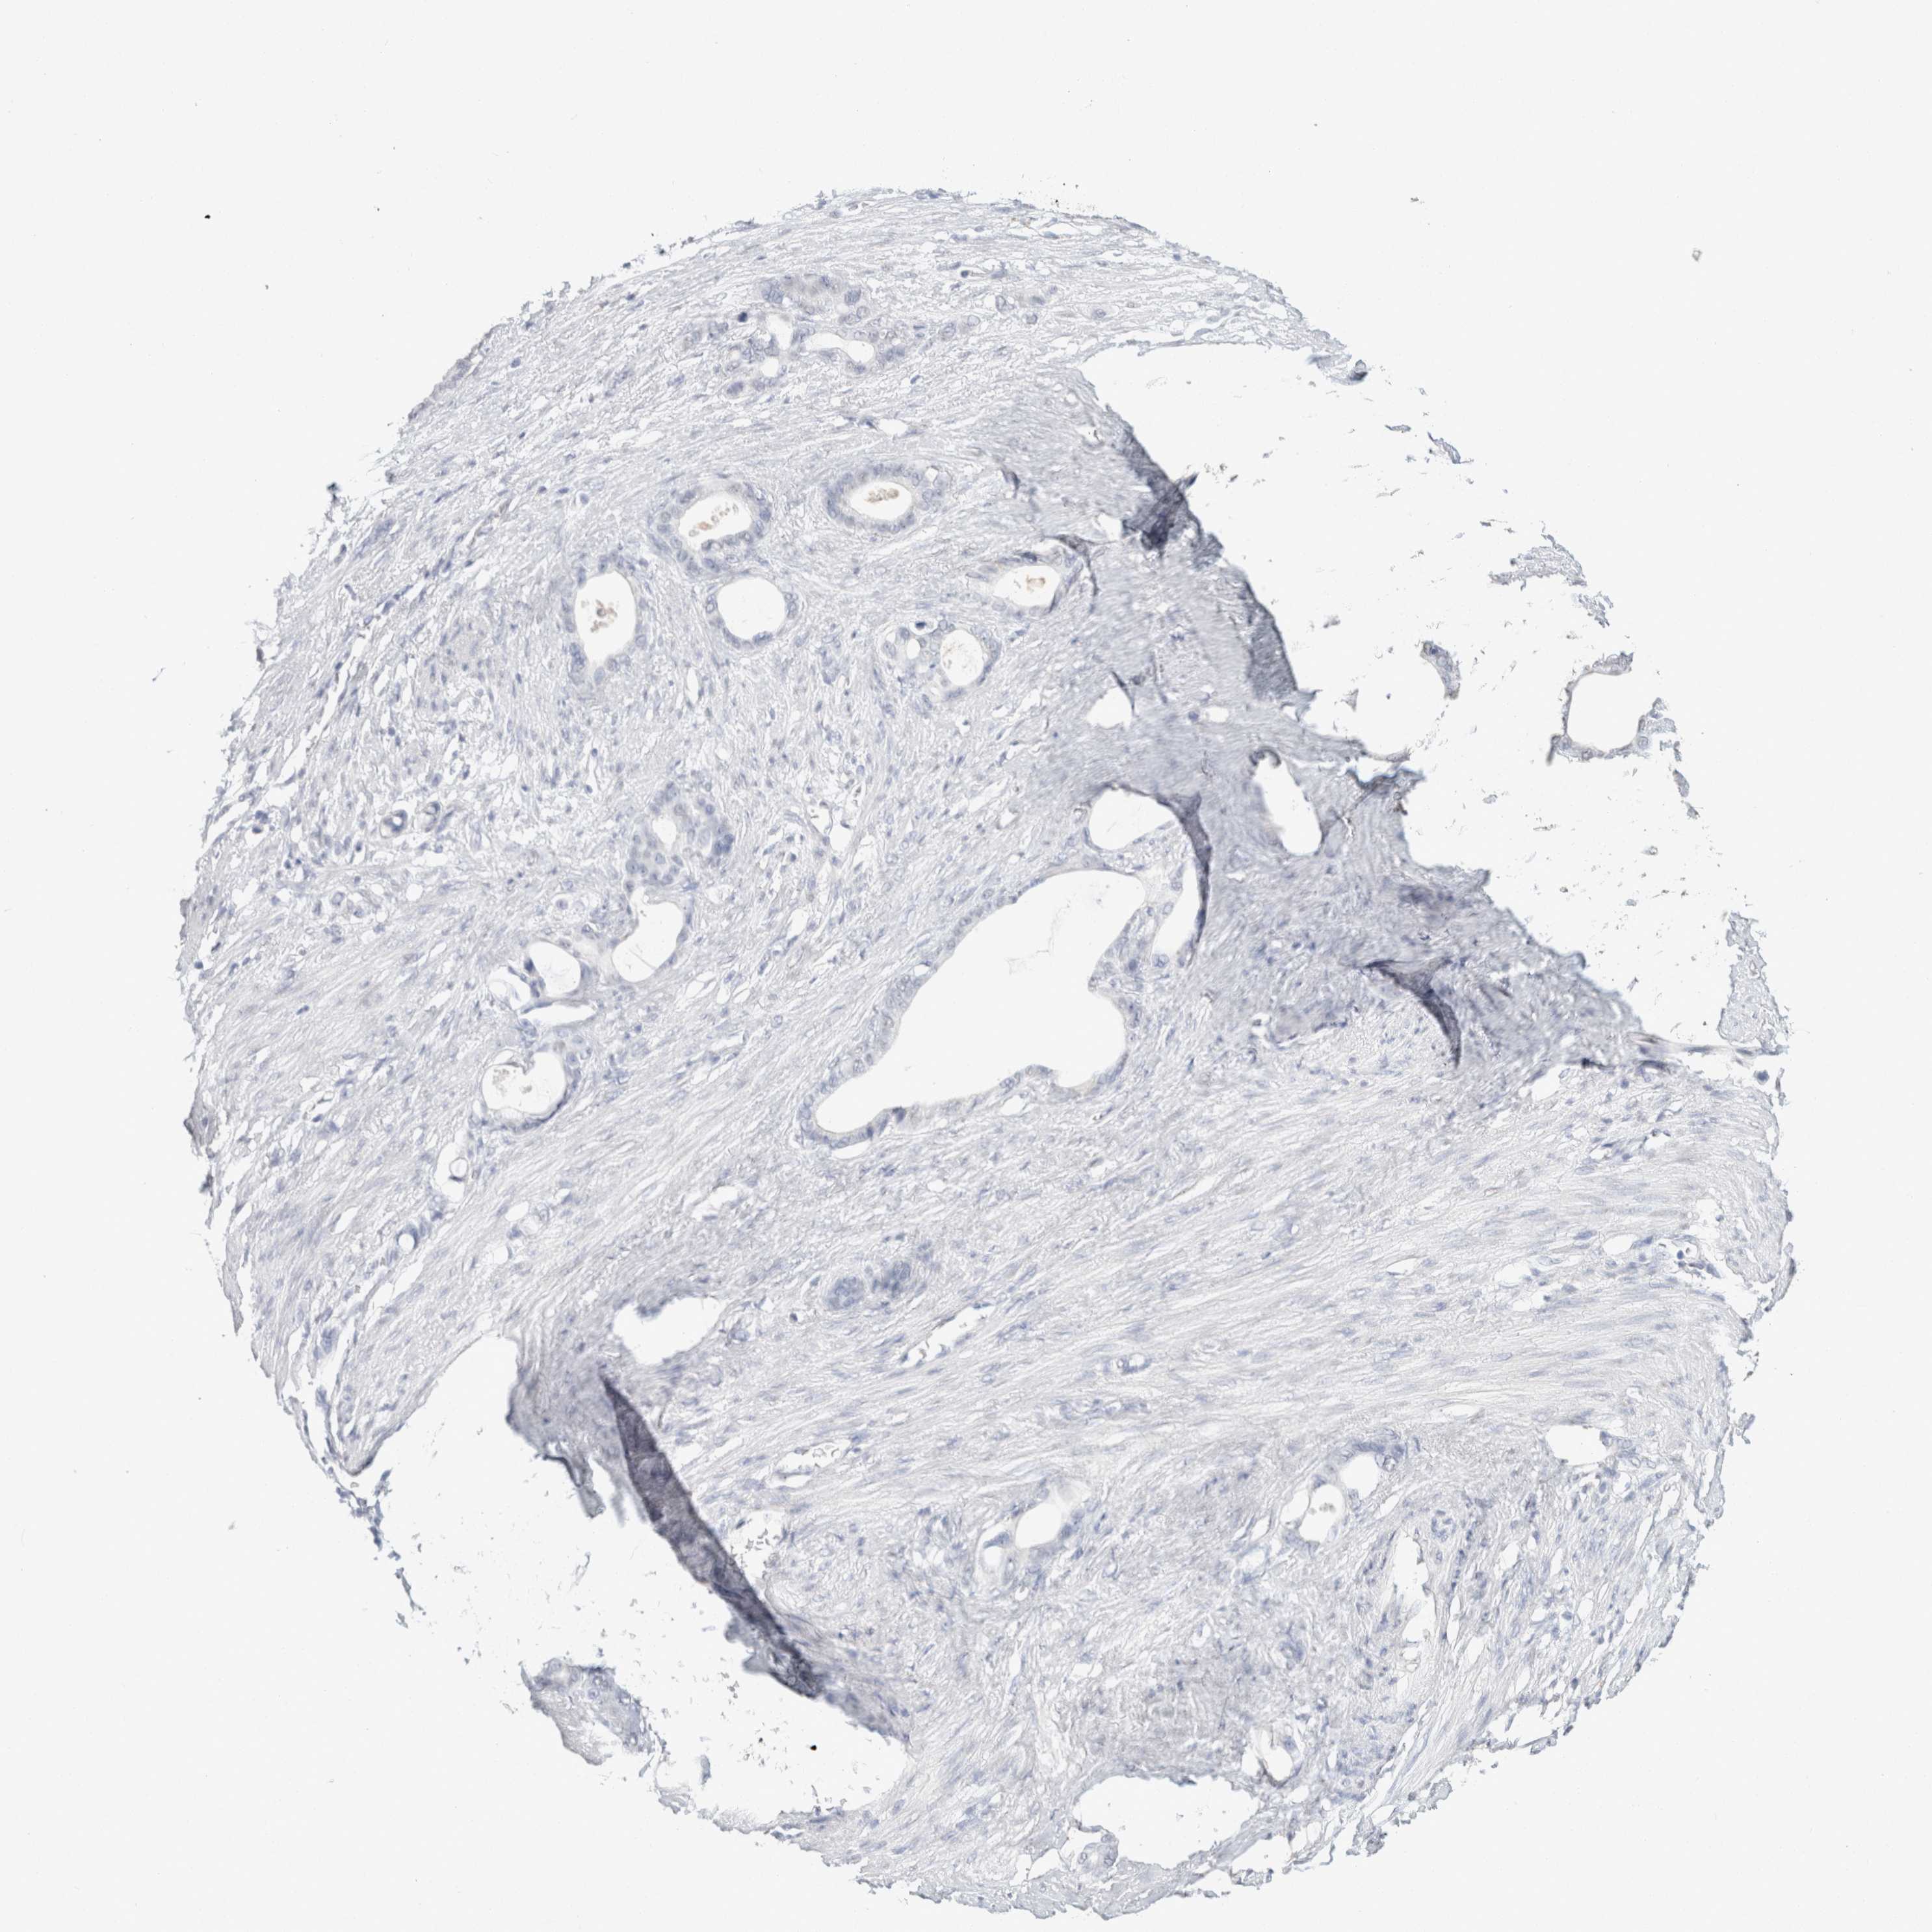

STOMACH CANCER - Protein expressioni

A mouse-over function shows sample information and annotation data. Click on an image to view it in a full screen mode. Samples can be filtered based on level of antibody staining by selecting one or several of the following categories: high, medium, low and not detected. The assay and annotation is described here.

Note that samples used for immunohistochemistry by the Human Protein Atlas do not correspond to samples in the TCGA dataset.

Antibody stainingi

Antibody staining in the annotated cell types in the current human tissue is reported as not detected, low, medium, or high, based on conventional immunohistochemistry profiling in selected tissues. This score is based on the combination of the staining intensity and fraction of stained cells.

Each image is clickable and will lead to virtual microscopy that enables deeper exploration of all samples and also displays staining intensity scores, fraction scores and subcellular localization as well as patient and tissue information for each sample.

Antibody HPA050092

Antibody CAB025368

Staining

High

Medium

Low

Not detected

Intensity

Strong

Moderate

Weak

Negative

Quantity

>75%

75%-25%

<25%

None

Location

Nuclear

Cytoplasmic/membranous

Cytoplasmic/membranous,nuclear

Adenocarcinoma, NOS

Adenocarcinoma, High grade